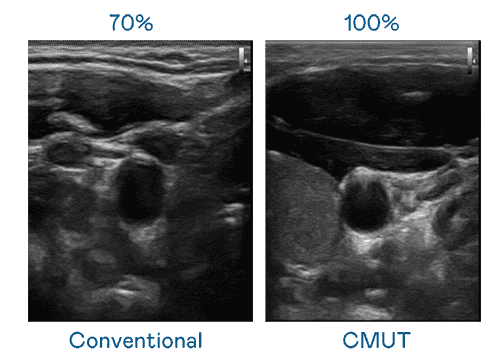

CMUT 技术是一种用电容式微机电元件来产生超音波讯号的技术。。。与传统 PZT 压电式技术相比,,,,CMUT 频宽增加 30%,,,更宽频的超音波讯号让影像解析度大幅提升,,,,是实现高影像品质医疗超音波扫描、、、促进精准医疗发展的关键技术。。。

超音波影像的解析度高低,,首先取决于探头能发出的讯号频宽。。尊龙z6 CMUT 可提供高清晰的超音波讯号,,提供高频宽、、、、高灵敏度、、、、影像纹理细节更高的超音波影像,,,,协助医护人员缩短影像判读时间及利用精准的医疗影像进行诊断。。。。